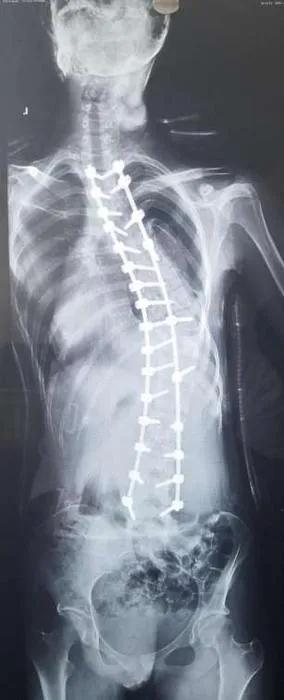

矫形后影像学图。(受访者供图)

“经过完善的术前检查与准备,入院后的第三天我们给小雅进行了脊柱侧弯后路截骨矫正术”,手术用时三个半小时”马原主任说,先采用薄层CT扫描,获得小雅的脊柱数据之后,再通过3D打印机打印出与人体椎体1:1的脊柱模型,最终通过术前设计好的置钉点和角度固定成模板导管,对患者的脊柱进行匹配,从而实现精准置钉的目的。